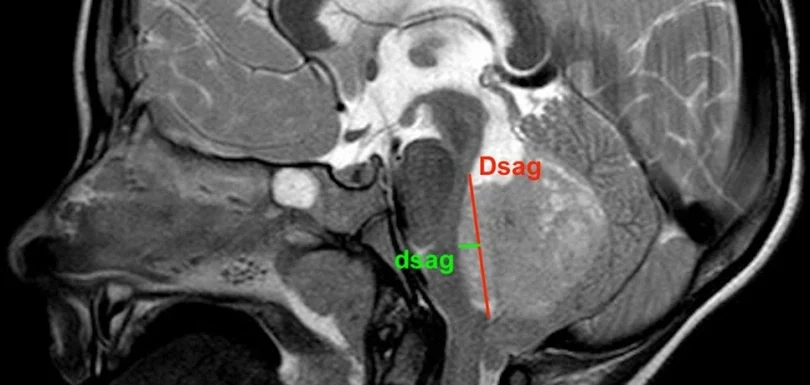

Posterior Fossa Tumors

Posterior Fossa Tumors Home At The Brain and Spine Centre, we specialize in the diagnosis and surgical treatment of neurological and spinal disorders. Dr. Muhammad Aqeel Natt, a leading neurosurgeon in Lahore, provides advanced, safe, and compassionate care for patients. Posterior fossa tumors require prompt, expert diagnosis and specialized surgical treatment to relieve symptoms and […]